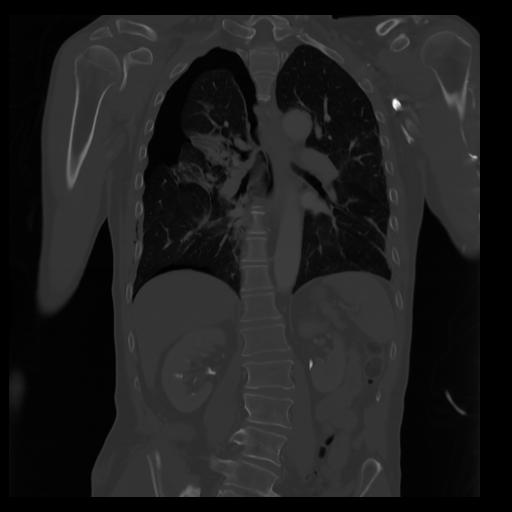

29 CUERPO,CE,Coronal,3.000,CUERPO,Coronal,